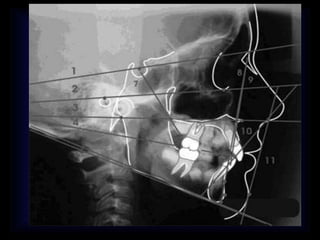

CEFALOMETRIA • A travésde los estudios cefalométricos, el ortodoncista logrará un conocimiento más profundo de las estructuras involucradas, medirlas, describirlas y estudiar sus interrelaciones. • La cefalometría no es una ciencia exacta, por las dificultades de localización de los puntos y la inexactitud de los exploradores a la hora de encontrarlos; no obstante es, junto a los modelos dentales, una de las principales herramientas diagnóstica en ortodoncia. • La cefalometría se realiza sobre un trazado obtenido del calco de líneas fundamentales de una radiografía lateral de cráneo, obtenida del paciente, según unas normas determinadas que nos permiten estandarizar los resultados y compararlos con patrones normales.

• 16.